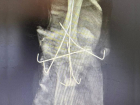

Ставропольские нейрохирурги провели сложную операцию по коррекции сколиоза 25.11.2025 Здоровье -